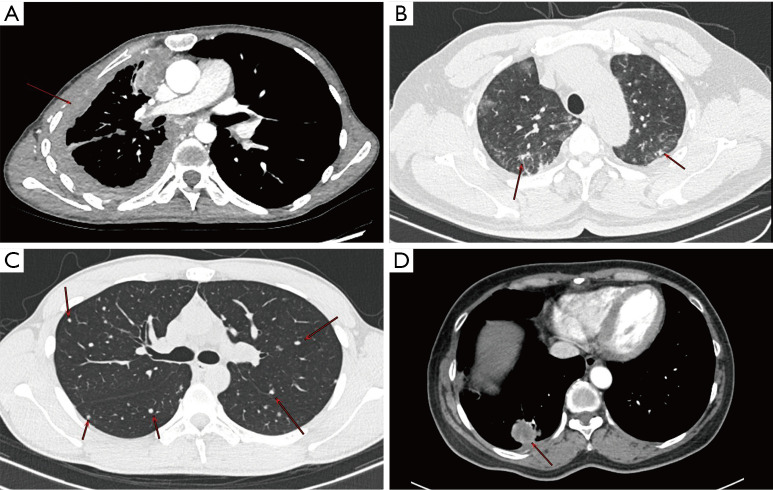

Figure 2.

Four imaging classifications of PEH according to the consensus. (A) Female, 28 years old, chest enhancement CT scan, mediastinal window cross-section shows diffuse uneven thickening of the right pleura (arrow). (B) Male, 52 years old, chest CT scan, lung window cross-section shows a multifocal fine reticular and nodular faint shadow in both lungs (arrow). (C) Male, 21 years old, chest CT scan, lung window cross-section shows multiple solid nodular shadows in both lungs (arrow). (D) Female, 55 years old, chest enhancement CT scan, mediastinal window cross-section shows a mass shadow in the posterior basal segment of the right lower lung, involving the right lower pleura (arrow). PEH, pulmonary epithelioid hemangioendothelioma; CT, computed tomography.